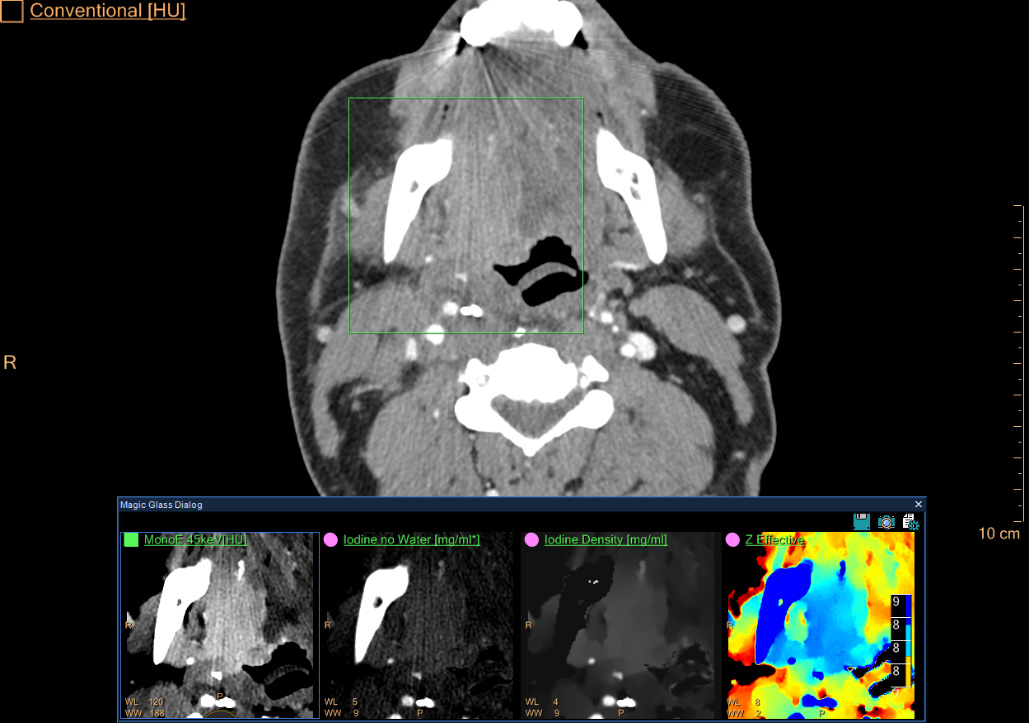

The ability to identify lesions in the neck can be difficult at times due to their location or artifacts from metal and bone. The IQon Spectral CT allows the use of multiple spectral results that can help enhance lesion visualization. IQon delivers diagnostic certainty using multiple layers of spectral data, allowing the first exam to be the right exam. In this case, a middle-aged female undergoing treatment for head and neck cancer received a follow-up scan on the IQon Spectral CT. A lesion at the base of the tongue on the right side was difficult to detect using conventional CT images only. MonoE 50 keV spectral results allowed the clinician to visualize the lesion boundaries, differentiating it from the surrounding tissue. Additional spectral results such as Z Effective, coupled with the Spectral Magic Glass feature, enabled additional layers of spectral information as well as simultaneous viewing and quick comparison of up to five different spectral results for a region of interest.